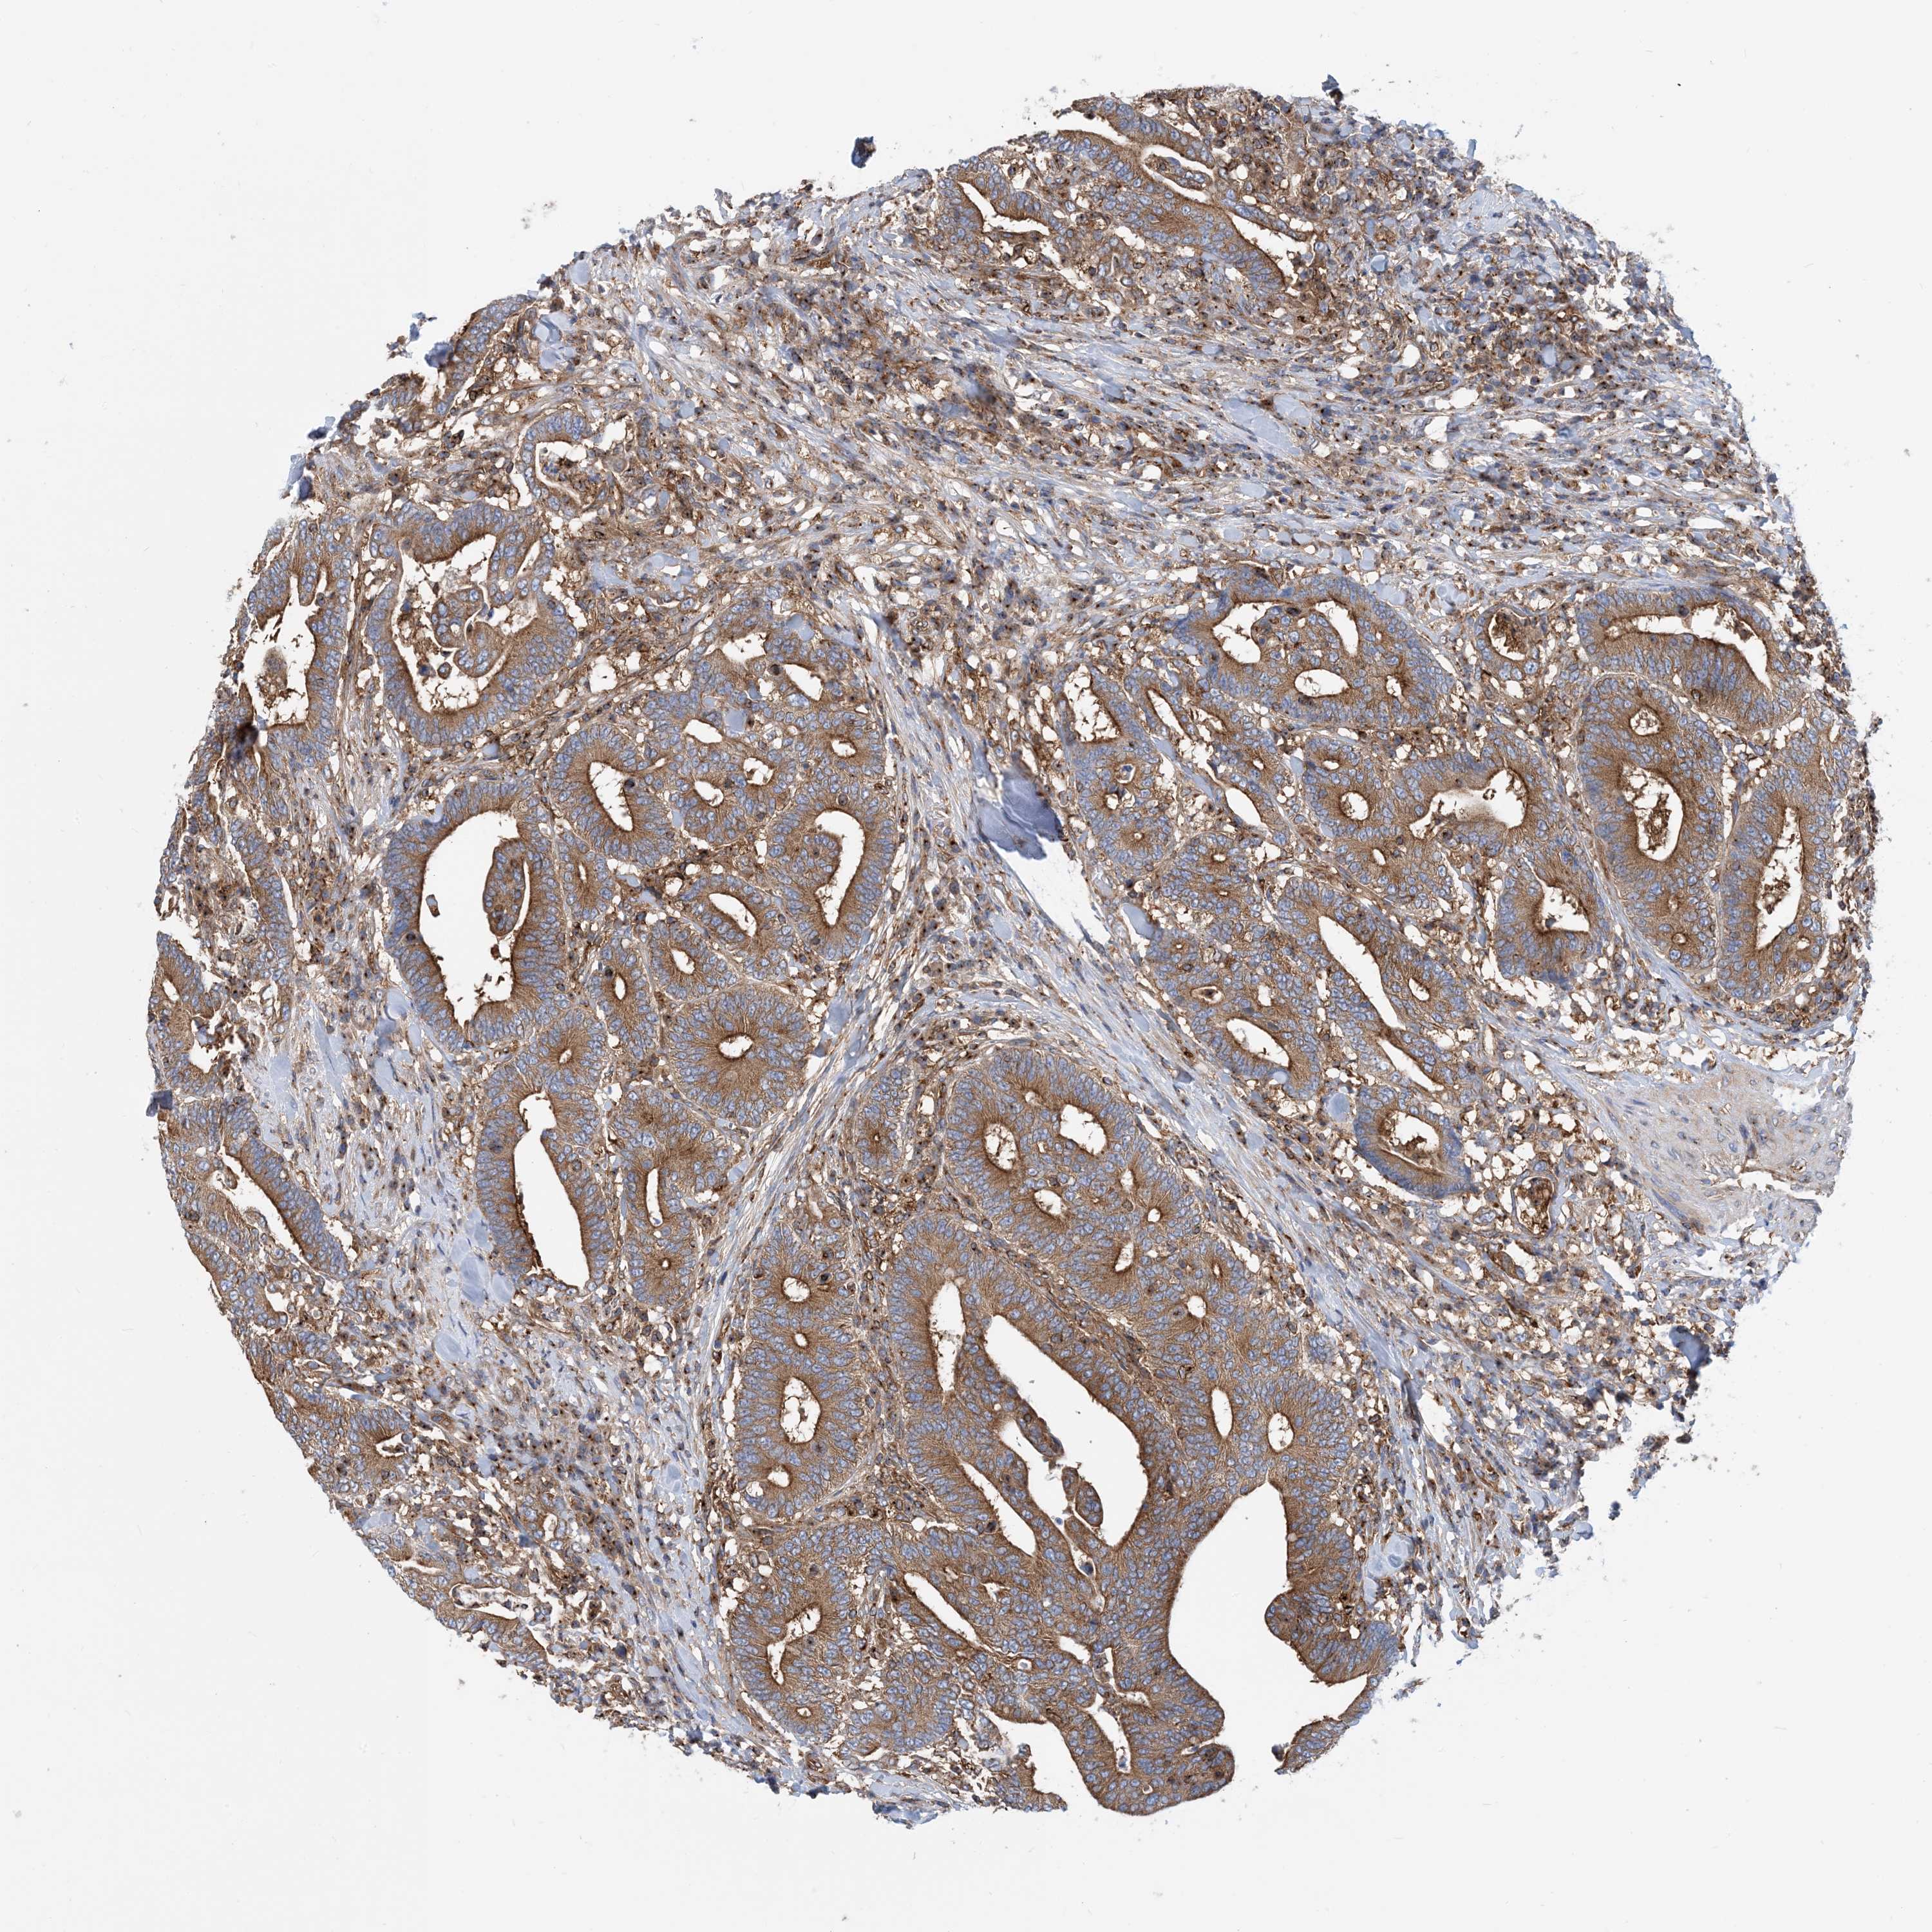

CANCER COLORECTAL CANCER Show tissue menu

Colorectal cancer

Human cancer

Colon adenocarcinoma